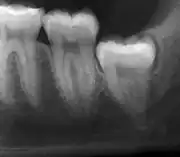

Panoramic radiograph of impacted lower wisdom teeth (green arrows) in a 26-year-old with dental caries (red arrows) on the adjacent teeth

The diagnosis of impaction can be made clinically if enough of the wisdom tooth is visible to determine its angulation, depth, and if the patient is old enough that further eruption or uprighting is unlikely. Wisdom teeth continue to move to the age of 25 years old due to eruption, and then continue some later movement owing to periodontal disease.[18]

If the tooth cannot be assessed with clinical exam alone, the diagnosis is made using either a panoramic radiograph or cone-beam CT. Where unerupted wisdom teeth still have eruption potential several predictors are used to determine the chance of the teeth becoming impacted. The ratio of space between the tooth crown length and the amount of space available, the angle of the teeth compared to the other teeth are the two most commonly used predictors, with the space ratio being the most accurate. Despite the capacity for movement into early adulthood, the likelihood that the tooth will become impacted can be predicted when the ratio of space available to the length of the crown of the tooth is under 1.[5]:141